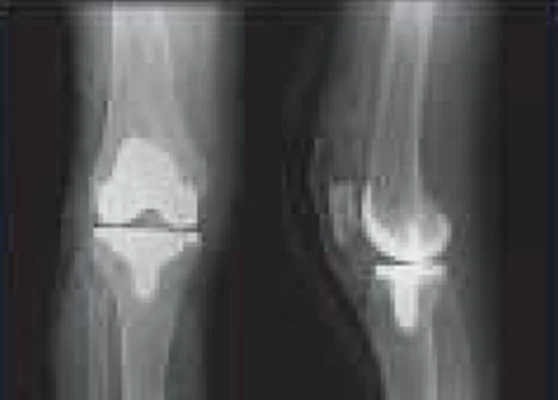

Xray before the surgery

X-ray

This helps the surgeon in seeing the damage initially before moving to the scanning stage.

X-rays are taken of AP standing, PA Flexion, Lateral and Sunrise position depending on case severity.

xray or implant Post surgery by LEO2 by Stryker Mako